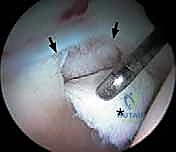

بمجرد دخول الكاميرا، يتم عرض صورة مكبرة وعالية الدقة (4K) لداخل المفصل على شاشة كبيرة. يقوم الدكتور هطيف بفحص جميع الهياكل بدقة متناهية: الغضروف المفصلي، الشفا الحقي، الرباط المدور، والبحث عن أي التهابات أو أجسام سائبة. يتم استخدام سائل ملحي معقم لضخ المفصل، مما يوسع المساحة ويغسل الدم لضمان رؤية واضحة تماماً.

* إصلاح الشفا الحقي (Labral Repair): إذا كان الشفا ممزقاً ولكن نسيجه لا يزال جيداً، يتم إعادة تثبيته في حافة الحُق باستخدام خطاطيف صغيرة جداً (Suture Anchors) تزرع في العظم وتمرر خيوطاً قوية لربط النسيج الممزق.

* تنظيف الشفا (Labral Debridement): إذا كان النسيج الممزق تالفاً جداً ولا يمكن خياطته، يتم تشذيبه وإزالة الأجزاء المتهتكة لتخفيف الألم ومن